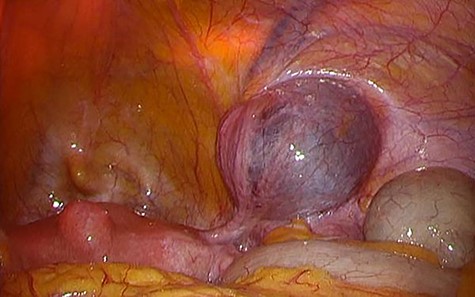

A 49-year-old woman presented with painless swelling in her right inguinal region. She had a history of caesarian section and no history of infantile inguinal hernia. Physical examination revealed a soft egg-shaped mass extending from the right inguinal region to the labia majora. The mass was seen as a protrusion when the patient was in the standing position, while it disappeared when the patient was in the lying position. Ultrasound revealed a well-defined hypo-echoic elongated mass that extended from the superficial inguinal canal, with no solid component (Fig. 1). Computed tomography (CT) showed that 55 × 34 × 95 mm oval fluid collection located at the right inguinal region near the cecum and retroperitoneum in the abdominal cavity (Fig. 2). Total colonoscopy found no mucosal abnormalities from the cecum to the rectum; however, a mass of tissue pushed the cecal wall from outside (Fig. 3). This hinted toward a large HCN, appendiceal tumor or retroperitoneal tumor; we decided to attempt a combined approach of conventional and laparoscopic methods for diagnosis and treatment of the swelling. We used three ports (12, 10 and 5 mm; Fig. 4) for our laparoscopic approach. We placed a 12 mm laparoscopic trocar into the umbilicus for CO2 insufflation of the pneumoperitoneum. Endoscopic intraperitoneal observation revealed that the mass was distant from the cecum and outside the peritoneum (Fig. 5). The tumor was large and was not completely observed using only an intra-abdominal approach. Therefore, we used a combined approach, which was the conventional method with a skin incision in the inguinal region in addition to the intra-abdominal method with laparoscopic approach. The tumor could be resected without any damage by observing from both directions (Fig. 6). We adopted the Direct Kugel Patch (ONFLEX®, C.R. Bard, Inc., USA) for the vulnerability of the posterior wall of the inguinal canal. Histopathological examination revealed that the mass contained single-layered mesothelial cells and no tumor or endometriosis. Based on imaging, histopathology and operative findings, we diagnosed her with an HCN. The patient recovered and did not have any postoperative complications, and she was discharged from hospital on postoperative day 6. She had no recurrence of hernia or hydrocele until 16 months postoperatively.